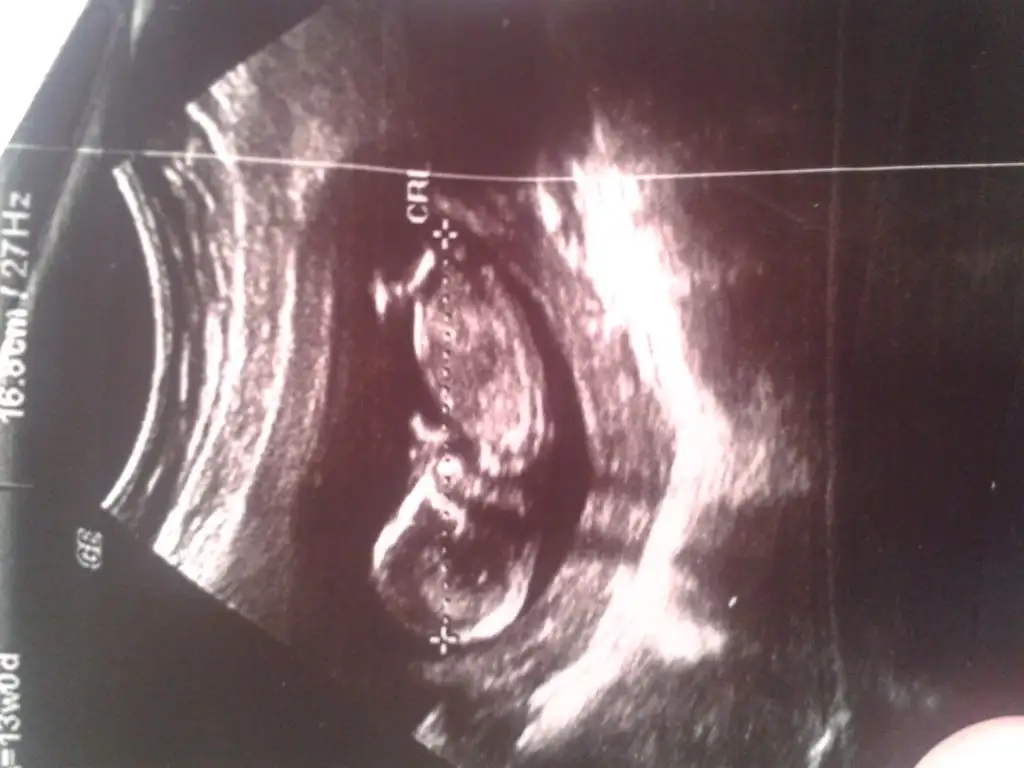

dr soylemeden siz gorun genital nub teorisi ( bebegin cinsiyeti)

kızlar doktordan yeni geldim ama 13+4 günlük cinsiyet tahmini icin erken dedi. Sizce tahmininiz varmi ??

Mrb arkadaslar Dr dan geliyom kıza benzettim dedi ama kesin degil dedi frikik vermiyo dedi bacakları birbirine cok yakın dedi bide cinsel organın orasında cizgi görürsek kız dıyoruz dedi benimkinde görmüş

Cinsiyetine bakıyo ya hani uzun uzun baktı arayı goremıyom bacaklar birbirine yakın dedi bakarken popoya dogru giden bi çizgi kızların oyle oluyomuş ama kesin degıl dedi

Kesin dememis bacaklari kapaliysa yanilma ihtimali vardir yinede herşeyin hayirlisi ama senin bebisin nubu gayet dik duruyordu